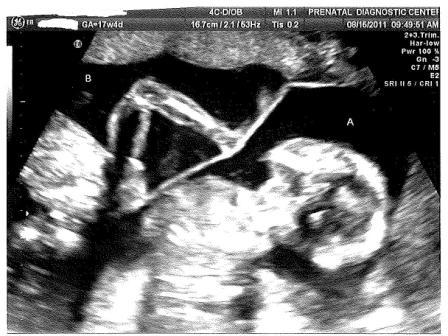

It’s a Girl and Another Girl! This entry was posted on August 25, 2011, in Pregnancy and tagged baby, clomid, kick, kicking baby, Pregnancy, sonogram, twin, twin girls, twin pregnancy, twins. Bookmark the permalink. Leave a comment We are proud to announce we are having 2 girls! Here’s Baby B kicking Baby A. No kidding, we actually watched her kick her sister in the head during the sonogram! Here’s a sweet sonogram of Baby B. home Share this: Share on Facebook (Opens in new window) Facebook Share on X (Opens in new window) X Share on Pinterest (Opens in new window) Pinterest Email a link to a friend (Opens in new window) Email Share on Tumblr (Opens in new window) Tumblr Like Loading... Related